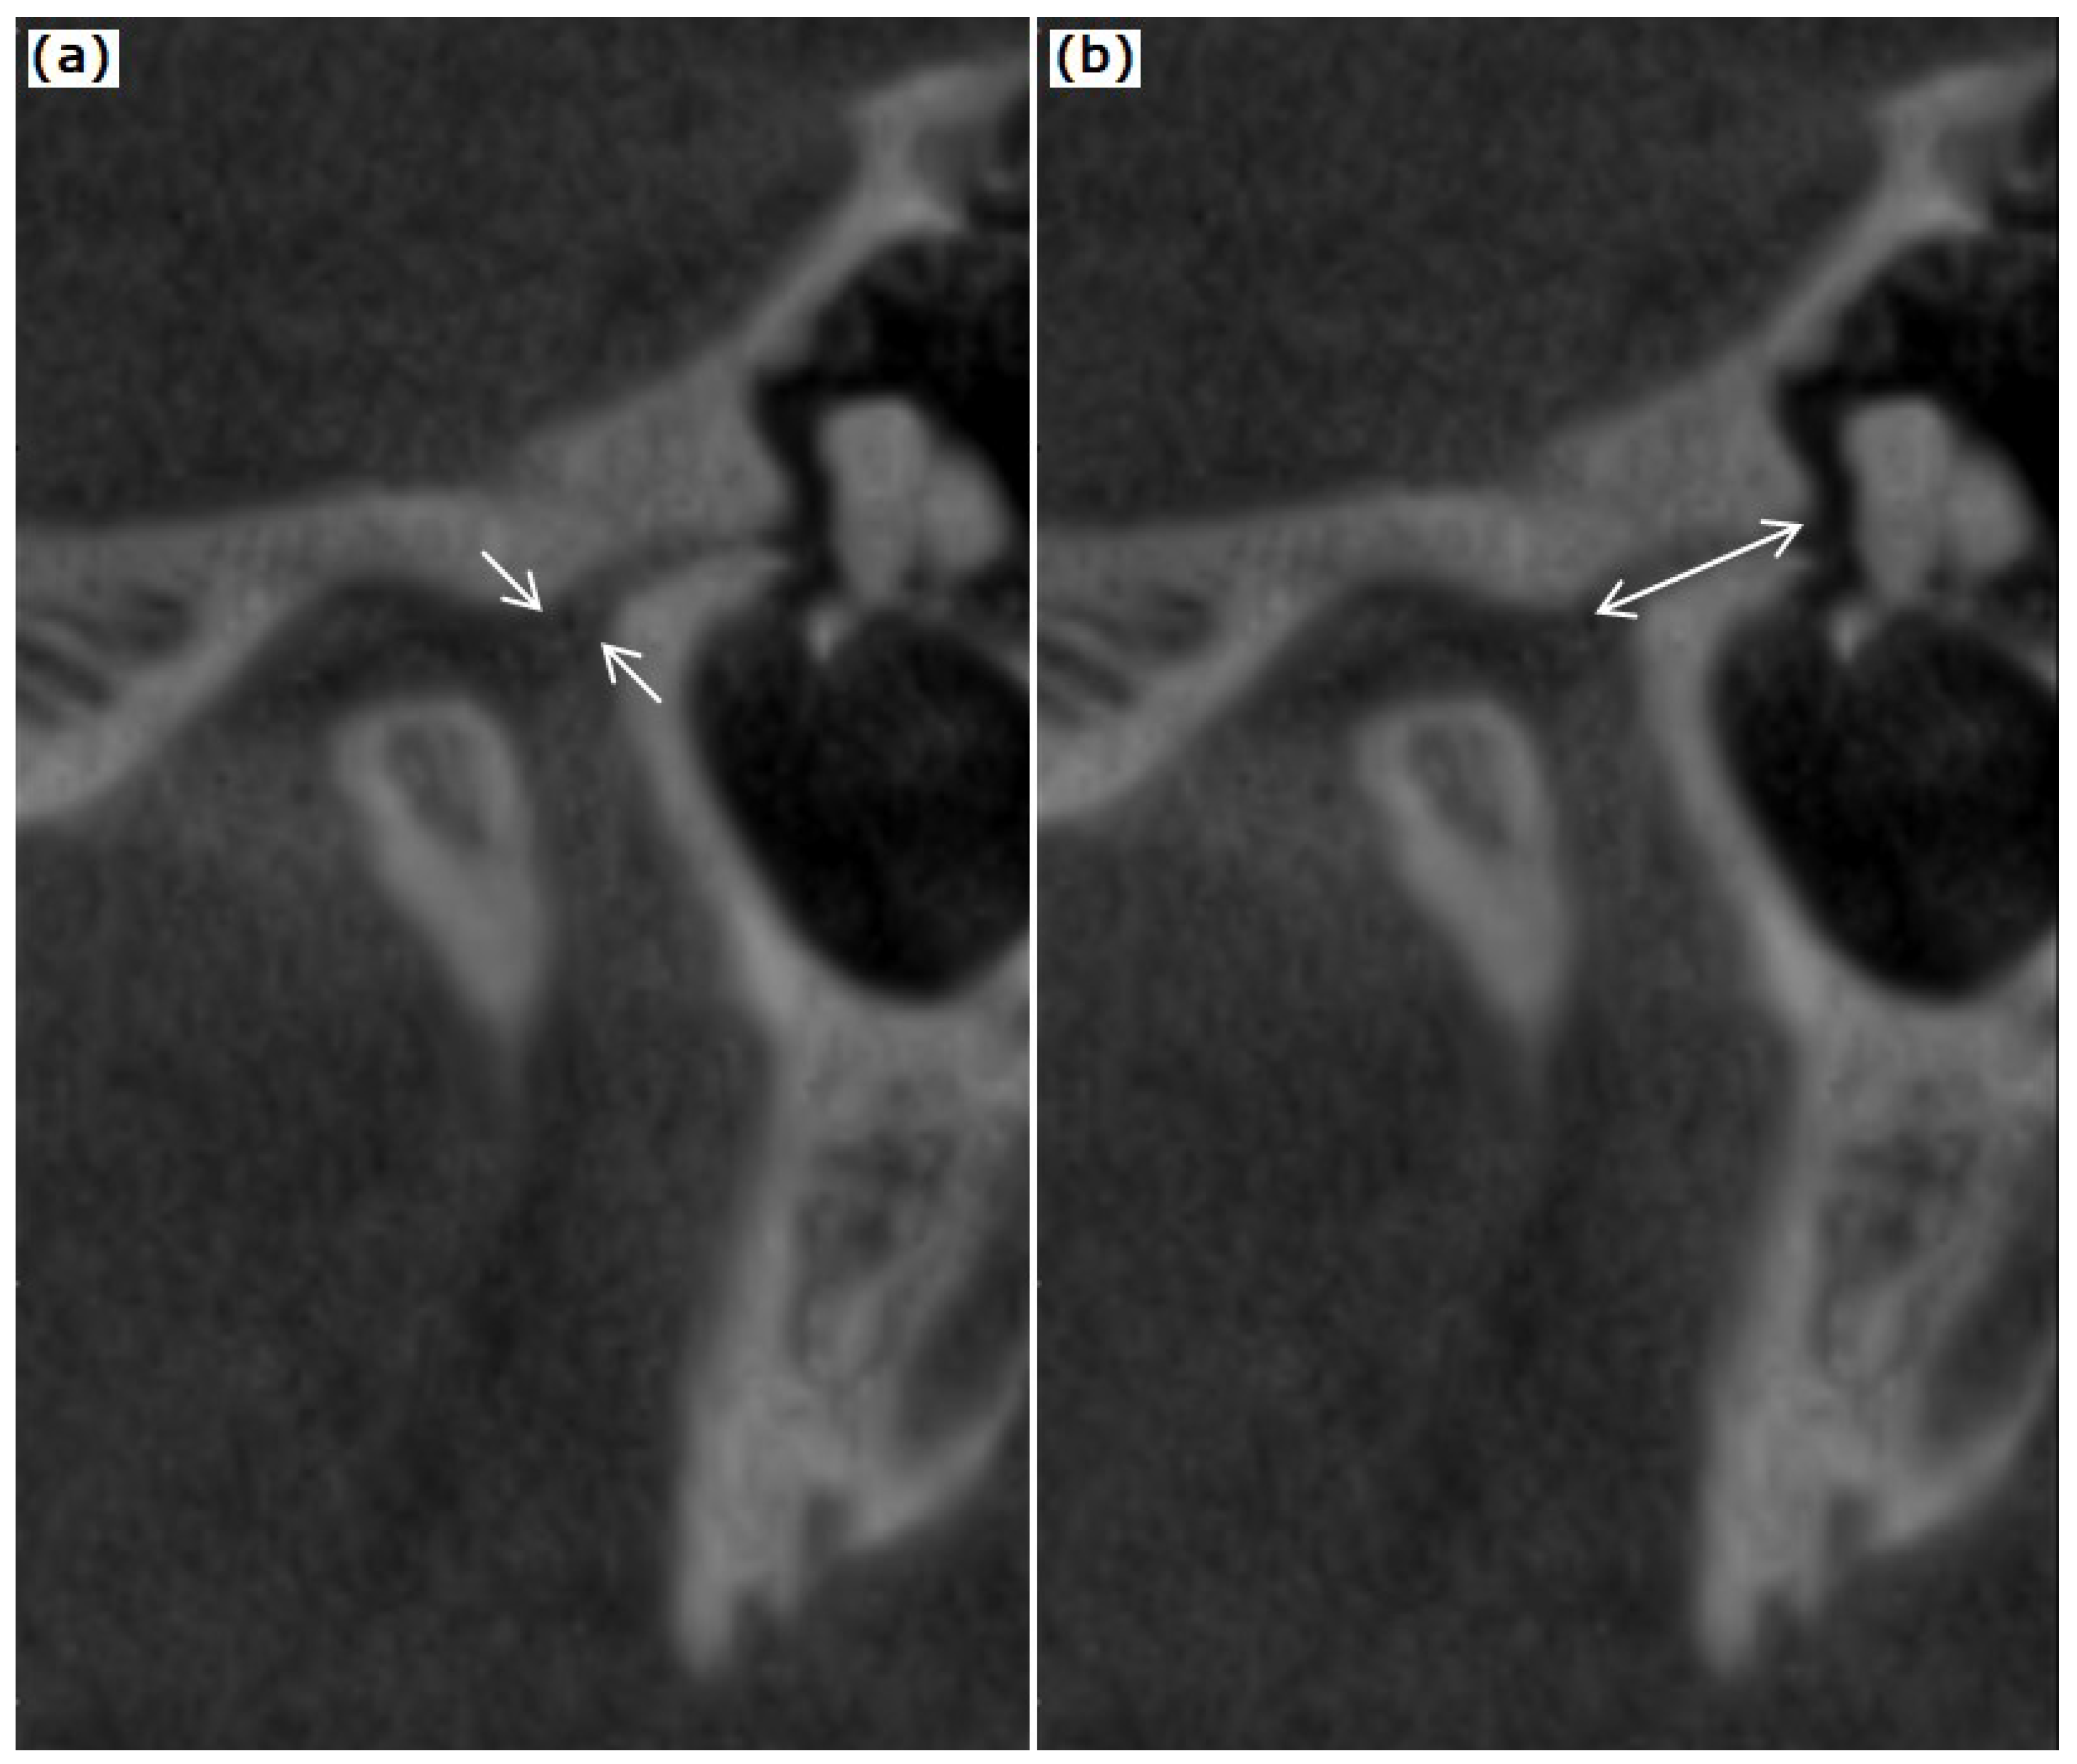

2.2. CBCT Examination of the TMJ and the Temporal Bone